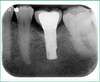

L'implant dentaire est une "nouvelle" racine :

L’implant dentaire, fabriqué en titane, est biologiquement inerte ou encore totalement bio-compatible, c'est à dire qu'il peut se lier durablement aux tissus vivants. (ostéointégration)